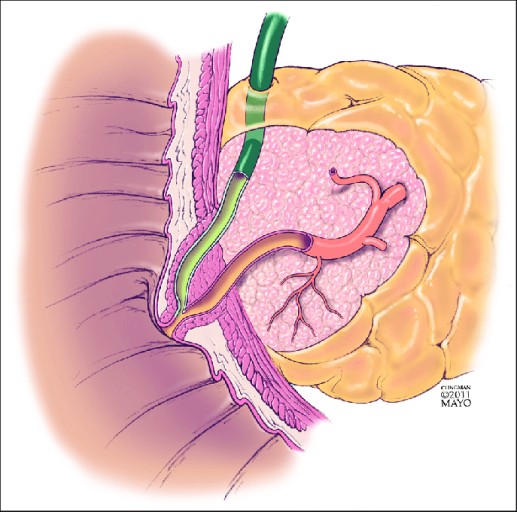

담석

음주 다음으로 췌장염을 일으키기는 주요 원인이 바로 담석이다. 담석이 담관 끝부분 및 췌관을 막게 되면, 담즙과 췌장액이 제대로 분비하지 못하게 되어 염증이 발생하게 됩니다. 염증으로 인해 급성 췌장염이 나타나고, 제대로 치료를 받지 못하다 보면 만성췌장염으로 진행될 가능성이 높아지는데요.